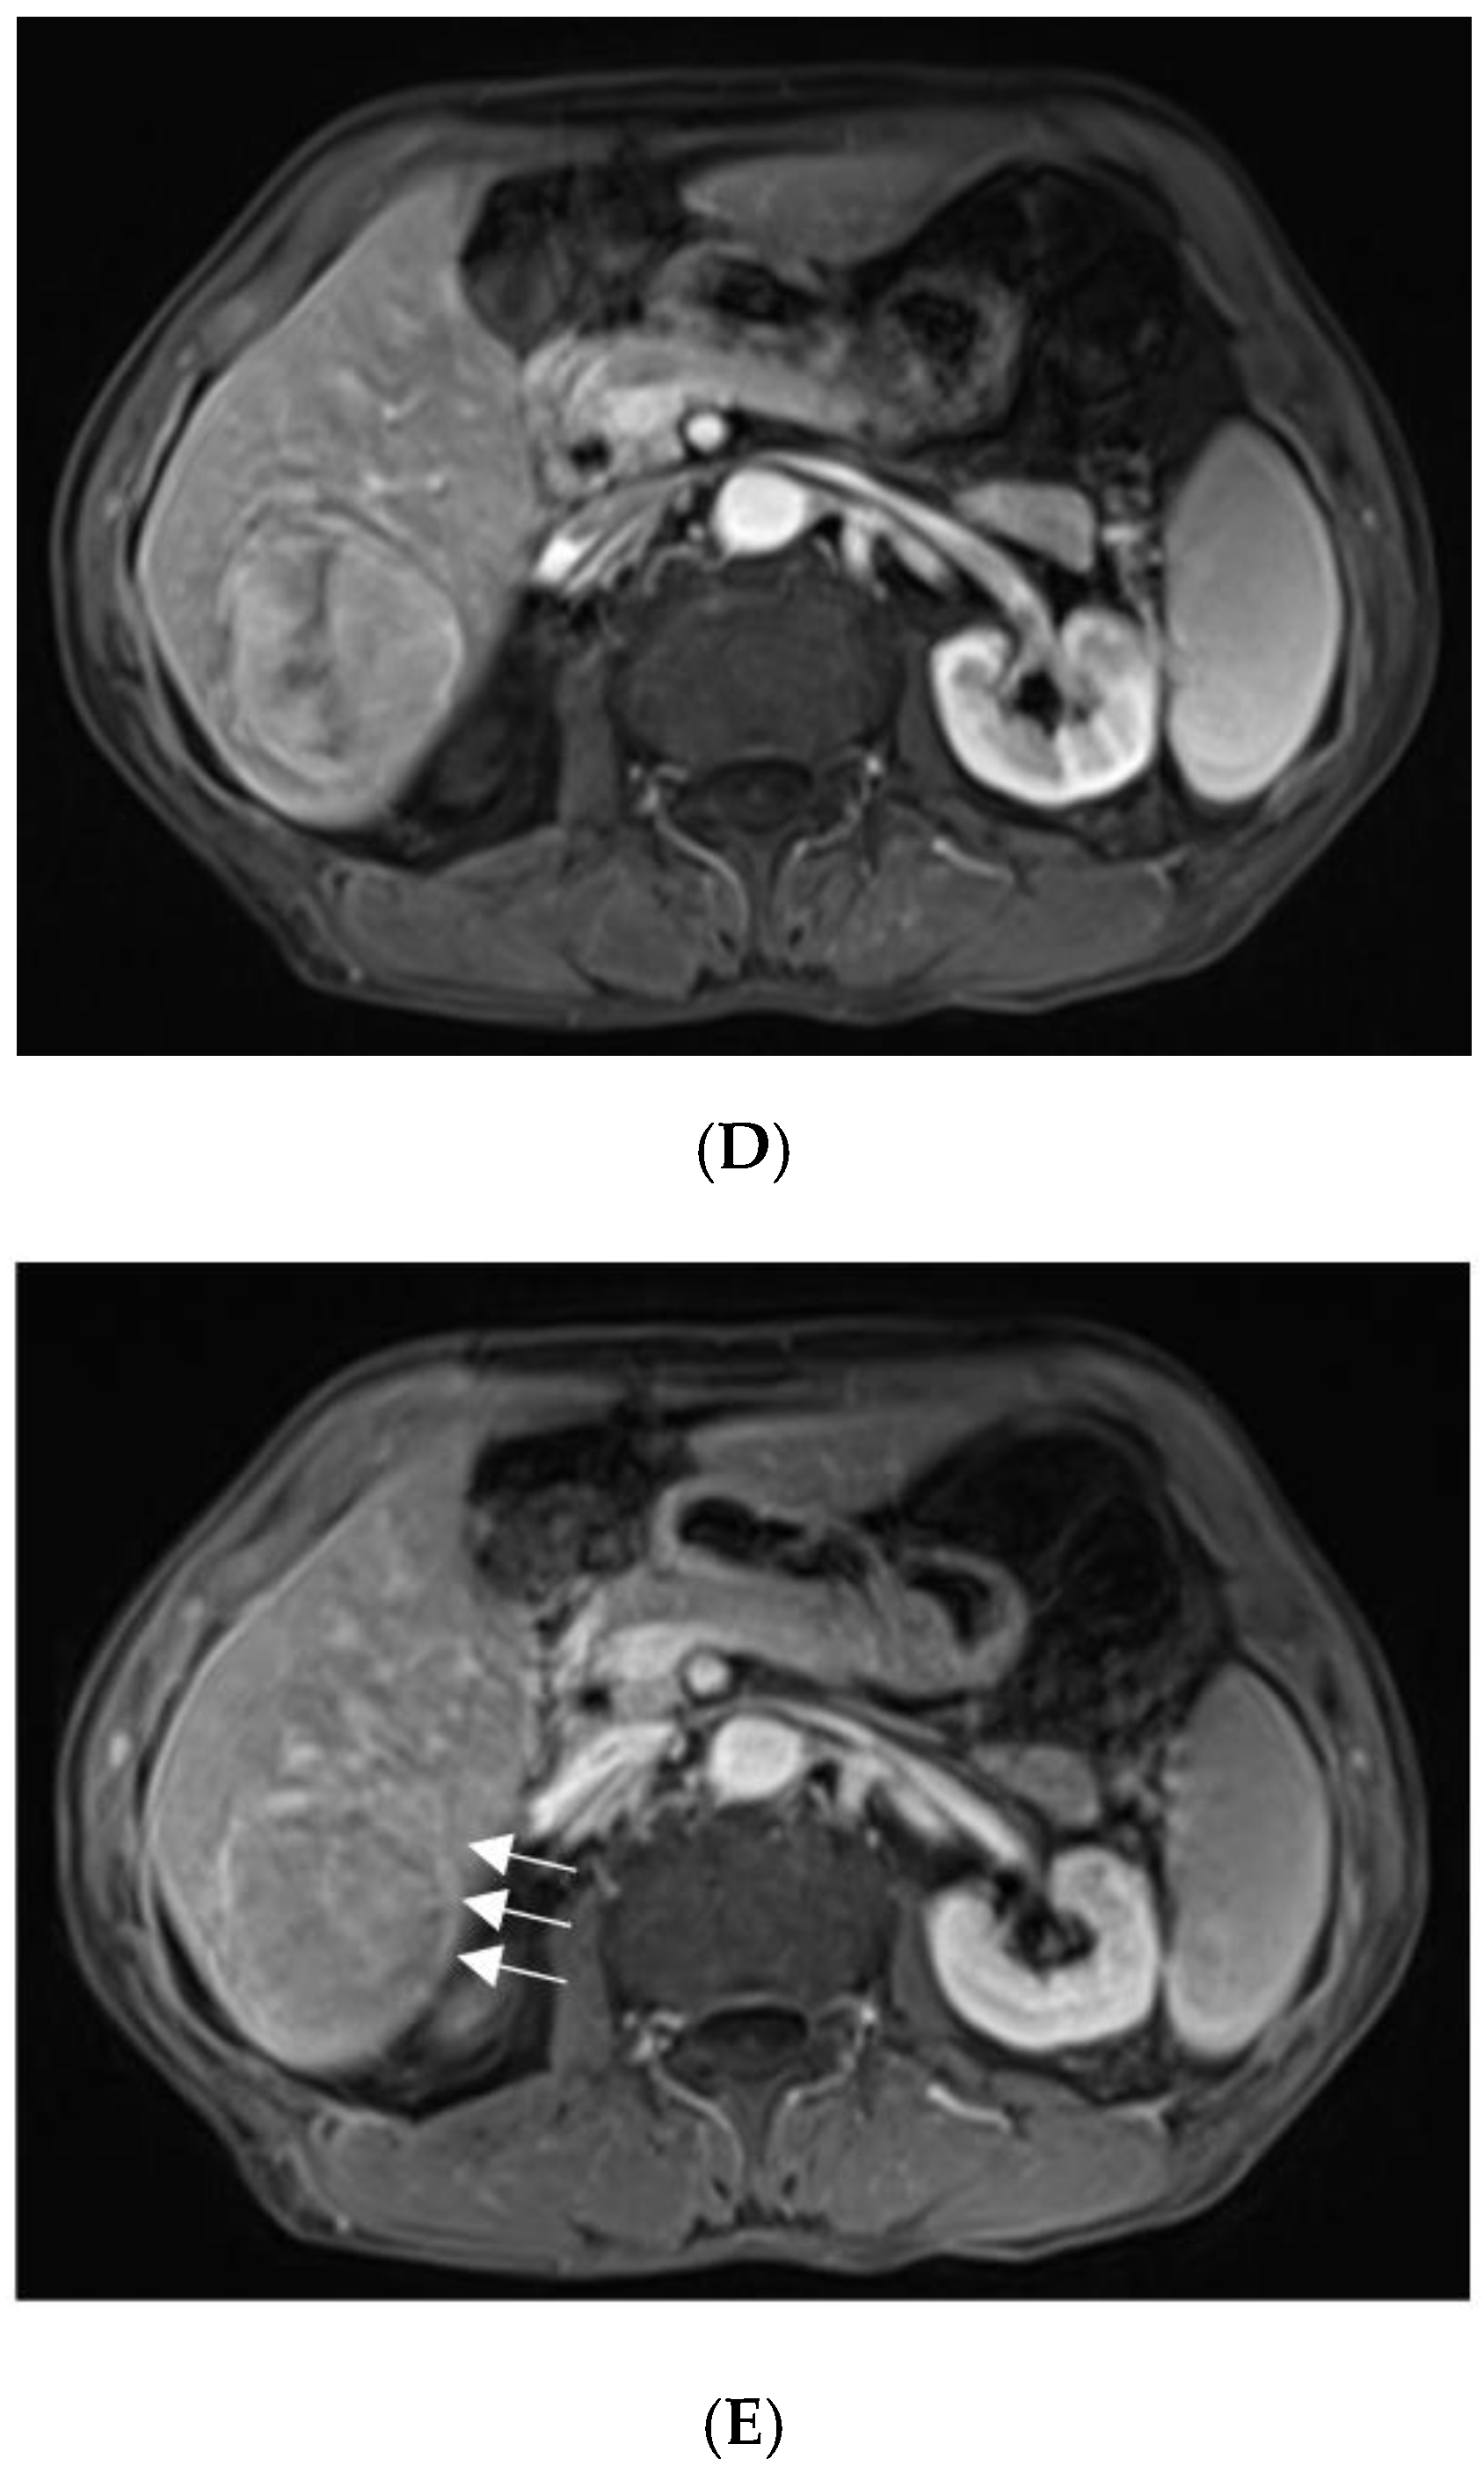

With suspicions of hepatocellular carcinoma (HCC), the patient was urged to undergo fluorine-18-fluro-2-deoxy-D-glucose-positron emission tomography/computed tomography (18F-FDG-PET/CT). The mass showed mild 18F-FDG uptake with SUVmax of 4.7 ((A), arrow). Moreover, hypermetabolic nodules in the lung, chest wall, thoracic vertebra, and pelvis were also observed, which indicated metastasis ((B–D), arrows).